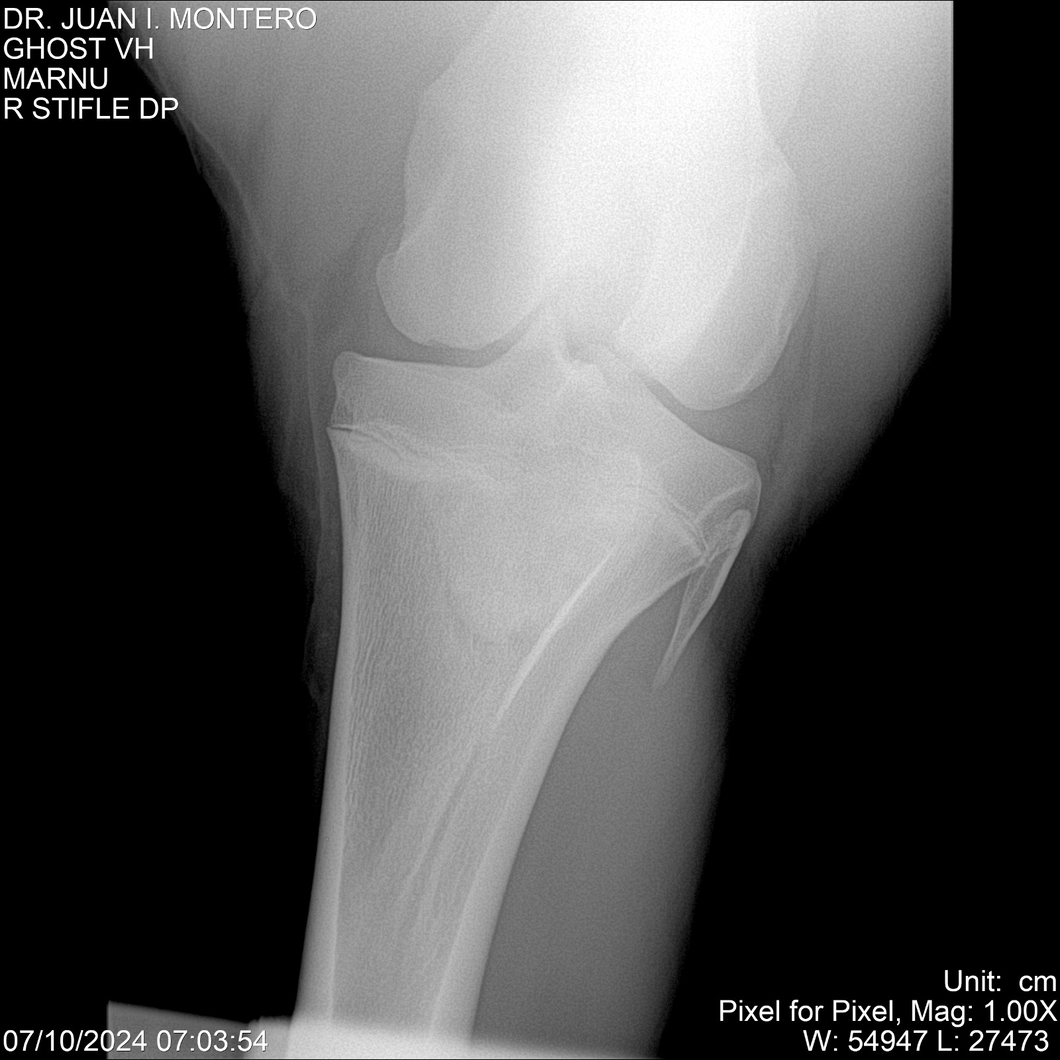

LOTE 15, GHOST VH 🔥 🔥 🔥 Lote Anterior Volver al remate Lote Siguiente Ficha Contacto Montevideo - Ficha del Lote Identificador: #282525 Categoría: Yeguarizos Montevideo - 69 Visualizaciones ClicData Contacto Empresa: Abelenda N. R., Walter Hugo Nombre*: Teléfono* : E-mail* : Mensaje Enviar Registrese gratis Este contenido Exclusivo está disponible sólo para usuarios registrados Ingresar